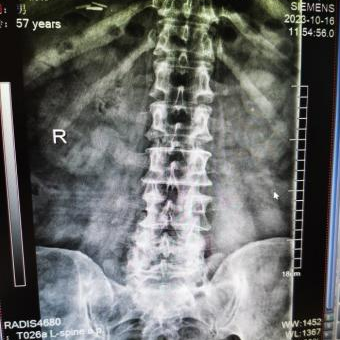

为提升区域内基层医疗机构糖尿病足诊疗服务能力、促进青年医师对糖尿病足的规范化诊治水平,遵义市第二城市医疗集团总院(贵州航天医院)圆满举办贵州省继续医学教育项目——胫骨横向骨搬移技术治疗糖尿病足专题研讨班。 贵州航天医院党委委员、副院长彭亮出席会议并致辞,遵义市第二城市医疗集团各成员单位,以及红花岗区、汇川区、绥阳县、桐梓县等多个区县的基层医疗机构骨干医师参加会议。 研讨班 本次研讨班以胫骨横向骨搬移技术在糖尿病足治疗中的应用为核心主题,围绕糖尿病药物治疗与生活方式管理策略、围手术期血糖精准调控要点、胫骨横向骨搬移技术典型病例深度解析、糖尿病足的临床分型与个体化治疗方案制定等临床实践中的热点与难点展开深入探讨,通过专题授课、案例研讨、互动交流等多元化形式,为参会者搭建了理论与实践结合的学习平台。 此次研讨班不仅为区域内基层医院搭建了学术交流与经验共享的平台,更对推动糖尿病足预防、诊断与治疗的规范化、系统化发展起到了积极作用,有效助力青年医师更新专业知识体系、提升临床技能,为进一步保障区域内糖尿病足患者的健康奠定了坚实基础。 贵州航天医院骨科专家简介 陈明勇 骨一科主任,副主任医师 临床擅长:从事创伤骨科工作约20年,对骨缺损、骨不连、骨肿瘤、肢体畸形等的肢体矫形重建及功能重建,慢性化脓性骨髓炎的根治治疗、糖尿病足的保肢治疗、快速康复理念(ERAS)下的老年骨折的诊治,四肢复杂骨折的诊治,四肢骨折等微创手术治疗具有丰富的临床经验。 2004年毕业于遵义医学院临床专业,曾在中国人民解放军总医院、广西医科大学第一附属医院、上海第六人民医院骨科进修。中国中西医结合学会骨伤科专业委员会横向骨搬移治疗糖尿病足及微血管网再生学组首届委员,遵义市医学会创伤分会常务委员。 瞿 晖 骨科党支部书记,骨二科主任,副主任医师 临床擅长:对骨科的常见病、关节外科、脊柱外科及运动医学疾病的诊治具有丰富的临床经验,熟练掌握骨科手术操作技术。 毕业于遵义医学院临床医学系,2005年前往广州中山大学第一附院骨显微医学部进修学习,2011年前往成都华西医院进修学习,并多次在省内外学习骨科相关知识,是中华医学会骨科分会会员。 赵小锋 中共党员,骨二科副主任,副主任医师 临床擅长:从事骨科临床工作11年,对骨科常见病、多发病诊疗有较为丰富的临床经验,擅长脊柱相关疾病诊断及治疗,尤其是颈、腰、腿疼痛疾病诊断及治疗,擅长胸腰椎骨折微创经皮穿刺内固定术、经皮穿刺椎体成形术、经皮穿刺脊柱内镜下腰椎间盘摘除术、单纯开创腰椎间盘摘除术、腰椎滑脱复位椎间植骨椎融合内固定术、腰椎管狭窄减压融合内固定术及人工髋、膝关节置换术等。 2012年毕业于遵义医学院外科学专业硕士研究生,2019年参加“遵义市115医学人才精英计划”于上海交通大学第一附属医院培训学习,2023年于北京大学第三人民医院脊柱外科进修学习,曾获得遵义市优秀医师荣誉称号。 遵义市手外科第一届委员,遵义市医学会创伤分会第一届委员,遵义市医学会创伤分会第二届委员,贵州省康复医学会第三届脊柱脊髓专业会委员,遵义市医学会烧伤与整形外科学分会委员,发表论文5篇,其中国家级核心期刊1篇,SCI论文1篇,主持市级课题1项并结题,参与市级课题2项。 赵兴东 骨科主任医师 临床擅长:擅长骨科的常见病及各种创伤、四肢骨折创伤修复、骨感染、手足疾病的诊治和手足体表畸形的矫形整复,熟练掌握骨科四肢骨病及创伤的手术操作技术,尤其在四肢关节复杂性损伤、手足外伤、组织缺损创面、难治创面的皮瓣修复方面及平足、高弓足矫形方面及四肢慢性疼痛诊治、康复方面具有丰富的临床经验。 硕士研究生,毕业于遵义医学院临床外科系,2015年前往山东省立医院手足外科进修学习;遵义市医学分会创伤分会第一、二届委员,遵义市手外科医学会第二委届员会常务委员;在省级及省级以上期刊发表文章9篇,参编著作2部,参与主持并完成市级课题1项,参与市级课题2项、省级课题1项。 张艳金 中共党员,骨科副主任医师 临床擅长:从事骨外科工作16年,对复合伤、多发伤的救治、四肢骨干骨折、关节周围骨折、骨肿瘤、骨髓炎等诊治具有丰富的临床经验。 中共党员,硕士研究生,2006年本科毕业于山西医科大学第二临床医学院,2011年研究生毕业于北京军区总医院;在“老年COPD患者合并髋部骨折的诊治”国际合作课题组研究两年,在老年髋部骨折的诊治方面具有丰富的经验,并发表论文6篇;主持遵义市级课题1项,承担遵义医科大学的临床教学工作,获得遵义医科大学优秀带教老师荣誉。编撰有《骨科疾病诊疗精粹》一书,开展2项新技术,编撰地方规范《务川自治县创伤骨科常见疾病诊疗规范》一书。 张俊凯 骨科副主任医师 临床擅长:从事骨科临床工作28年,对创伤骨折、骨感染、骨缺损、骨不连等外科诊治,四肢骨折的微创手术治疗,四肢复杂骨折(如关节内粉碎性骨折、多发骨折等)的损伤控制及手术治疗等具有丰富的临床经验。 1995年毕业于遵义医学院临床专业,2009年前往复旦大学附属医院骨科进修1年。 卢懿明 中共党员,骨科副主任医师 临床擅长:从事骨科工作18年,对创伤骨折、四肢骨折的微创手术治疗、四肢复杂骨折(如关节内粉碎性骨折、多发骨折等)的损伤控制及手术治疗,尤其是髋部骨折的PFNA等微创技术,踝关节骨折、膝关节周围骨折的Mipo微创技术等具有丰富的临床经验,开展了4项新技术,发明6项新型专利技术。 2005年毕业于遵义医学院临床专业,2017年,前往南方医科大学第三附属医院骨科进修半年,回院后运用Mipo技术对骨干骨折及干骺端骨折的治疗技术,同时积极开展骨盆骨折、髋臼骨折腹直肌外侧切口的应用;发表了多篇专业论文,经常参与省内外学术交流会授课,获得医院荣誉称号多个。 邬夏荣 骨科副主任医师 临床擅长:从事骨科工作16年,对四肢复杂骨折、骨肿瘤的诊治,尤其是足踝创伤、慢性踝关节损伤、平足症等诊疗具有丰富的临床经验。 2006年毕业于遵义医科大学临床医学专业,曾在陆军军医大学西南医院进修学习,发表多篇骨科学术论文。 余德怀 中共党员,骨科副主任医师 临床擅长:从事骨科工作10余年,对运动医学、骨关节、脊柱外科常见病、多发病的诊治具有丰富的临床经验。 硕士研究生,2011年毕业于遵义医学院临床医学专业,曾前往遵义医科大学附属医院运动医学专业进修学习;是贵州省医学会运动医学分会青年委员,西部关节镜联盟委员;发表多篇骨科学术论文。 冯 乾 骨科副主任医师 临床擅长:从事骨科工作近20年,熟练掌握骨科多发病及常见病的诊治,尤其对脊柱退变性疾病的诊断及治疗具有丰富的临床经验,主要研究脊柱微创相关治疗方式,能熟练开展椎间孔镜及UBE。 曾前往北京大学第三医院进修学习疼痛及椎间孔镜、首都医科大学友谊医院专业进修脊柱内镜;是贵州省康复医学会第三届脊柱脊髓专业委员会委员;发明专利3项、发表脊柱外科专业论文多篇。 贵州航天医院骨科简介 基本情况 贵州航天医院(原3417医院)骨科组建于1968年,前身是以创伤和断肢(断指)再植闻名于世的上海市第六人民医院骨科,中国断肢(断指)再植的奠基者、中科院院士陈仲伟等专家莅临科室指导医疗和教学,并在70年代开展了贵州省首例断肢(断指)再植手术。组建50余年来,诊治患者已逾百万,挽救了无数的伤病员,成为了保障遵义地区人民群众健康的重要支撑。 经过几代人的不懈努力,今天的骨科,已由创伤骨科发展至骨病、骨肿瘤、骨结核等领域,现有脊柱外科、关节外科、四肢创伤、手足外科四个亚专科,成为了集医疗、教学、科研于一体的综合学科,是贵州省临床重点专科、遵义市临床重点专科、遵义市骨科临床医学中心、遵义市基层骨科专科联盟理事长单位。 科室目前开放床位110张,共有医护人员50余人,副高级以上专家18人,硕士研究生15人。拥有一流骨科医疗设备多台,每年不定期选派优秀技术骨干到全国各大知名医学院校进修、学习、参观、交流,并邀请国内、国外知名专家教授来院进行交流、指导,通过不断引进国内外先进的诊疗技术,科室医疗技术水平稳步提升,为广大人民群众提供了优质的医疗服务。 专科特色 骨一科 (一)骨缺损、骨不连的肢体与功能重建 胫骨横向骨搬移技术治疗糖尿病足: (二)慢性骨髓炎的根治治疗 (三)肢体缺血性疾病如糖尿病足、脉管炎的保肢治疗 (四)皮瓣修复 (五)复杂创伤的治疗 (六)老年髋部骨折及小儿骨折快速手术 老年髋部骨折: 骨二科 (一)胸腰椎骨折微创经皮椎弓根螺钉固定术 (二)老年性骨质疏松性患者腰椎滑脱脊柱内固定术(骨水泥螺钉) (三)V形双通道脊柱内镜技术(VBE)腰椎融合术治疗腰椎退行性疾病 (四)老年性骨质疏松性骨折(PVP/PKP)术 (五)人工髋关节置换术 (六)双侧股骨头坏死人工全髋关节置换 (七)右侧全髋置换术后假体周围骨折翻修 (八)人工膝关节置换术 (九)人工膝关节假体松动翻修 (十)关节镜技术 传统手术切口 关节镜技术切口 诊疗范围 骨一科 1.四肢创伤、矫形。 2.手、足踝外科。 骨二科 End